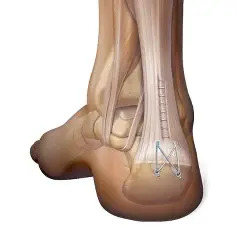

Achilles Tendon Reconstruction

Repairs damaged tendon to restore strength and function.